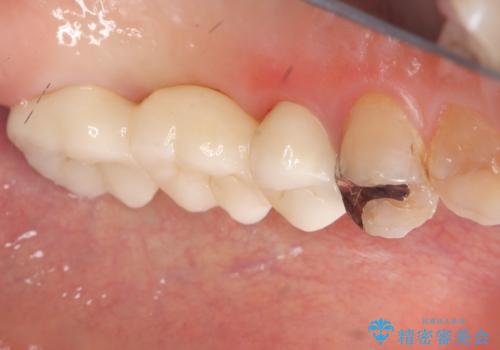

左上7番遠心マージン不適を認め、そこに汚れが停滞していたためやり替えをおすすめし、汚れが付着しずらく審美性に優れたセラミッククラウンブリッジでのやり替えとなりました。

保険適用のメタルインレーを除去したところ、ポンティック部の過度な加圧によって歯肉が強く発赤していたため、一度仮歯に置き換え歯肉の治りを待った後、適切な加圧強さのオールセラミッククラウンブリッジをセットしています。